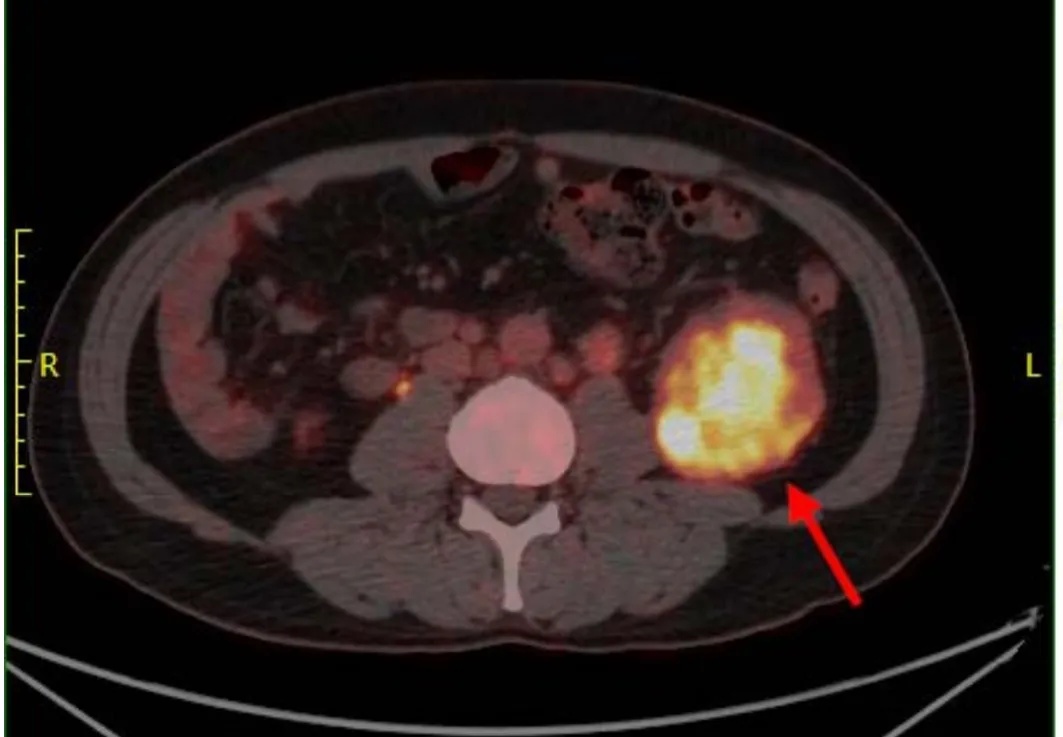

在医生和家属的反复劝说下,一直疏于体检的刘鑫终于同意住院好好查一查,这一查,结果让大家都倒吸一口冷气:左肾下极有一个7.6x8.2cm的占位,相当于一个鹅蛋大小,并且肾脏周围充斥着肿大的淋巴结,高度怀疑肿瘤。随后刘鑫进一步接受了全身PET-CT检查,结果考虑肾恶性肿瘤,左锁骨上、肾门区、腹膜后多处淋巴结肿大,全身骨质密度不匀,不排除骨转移。